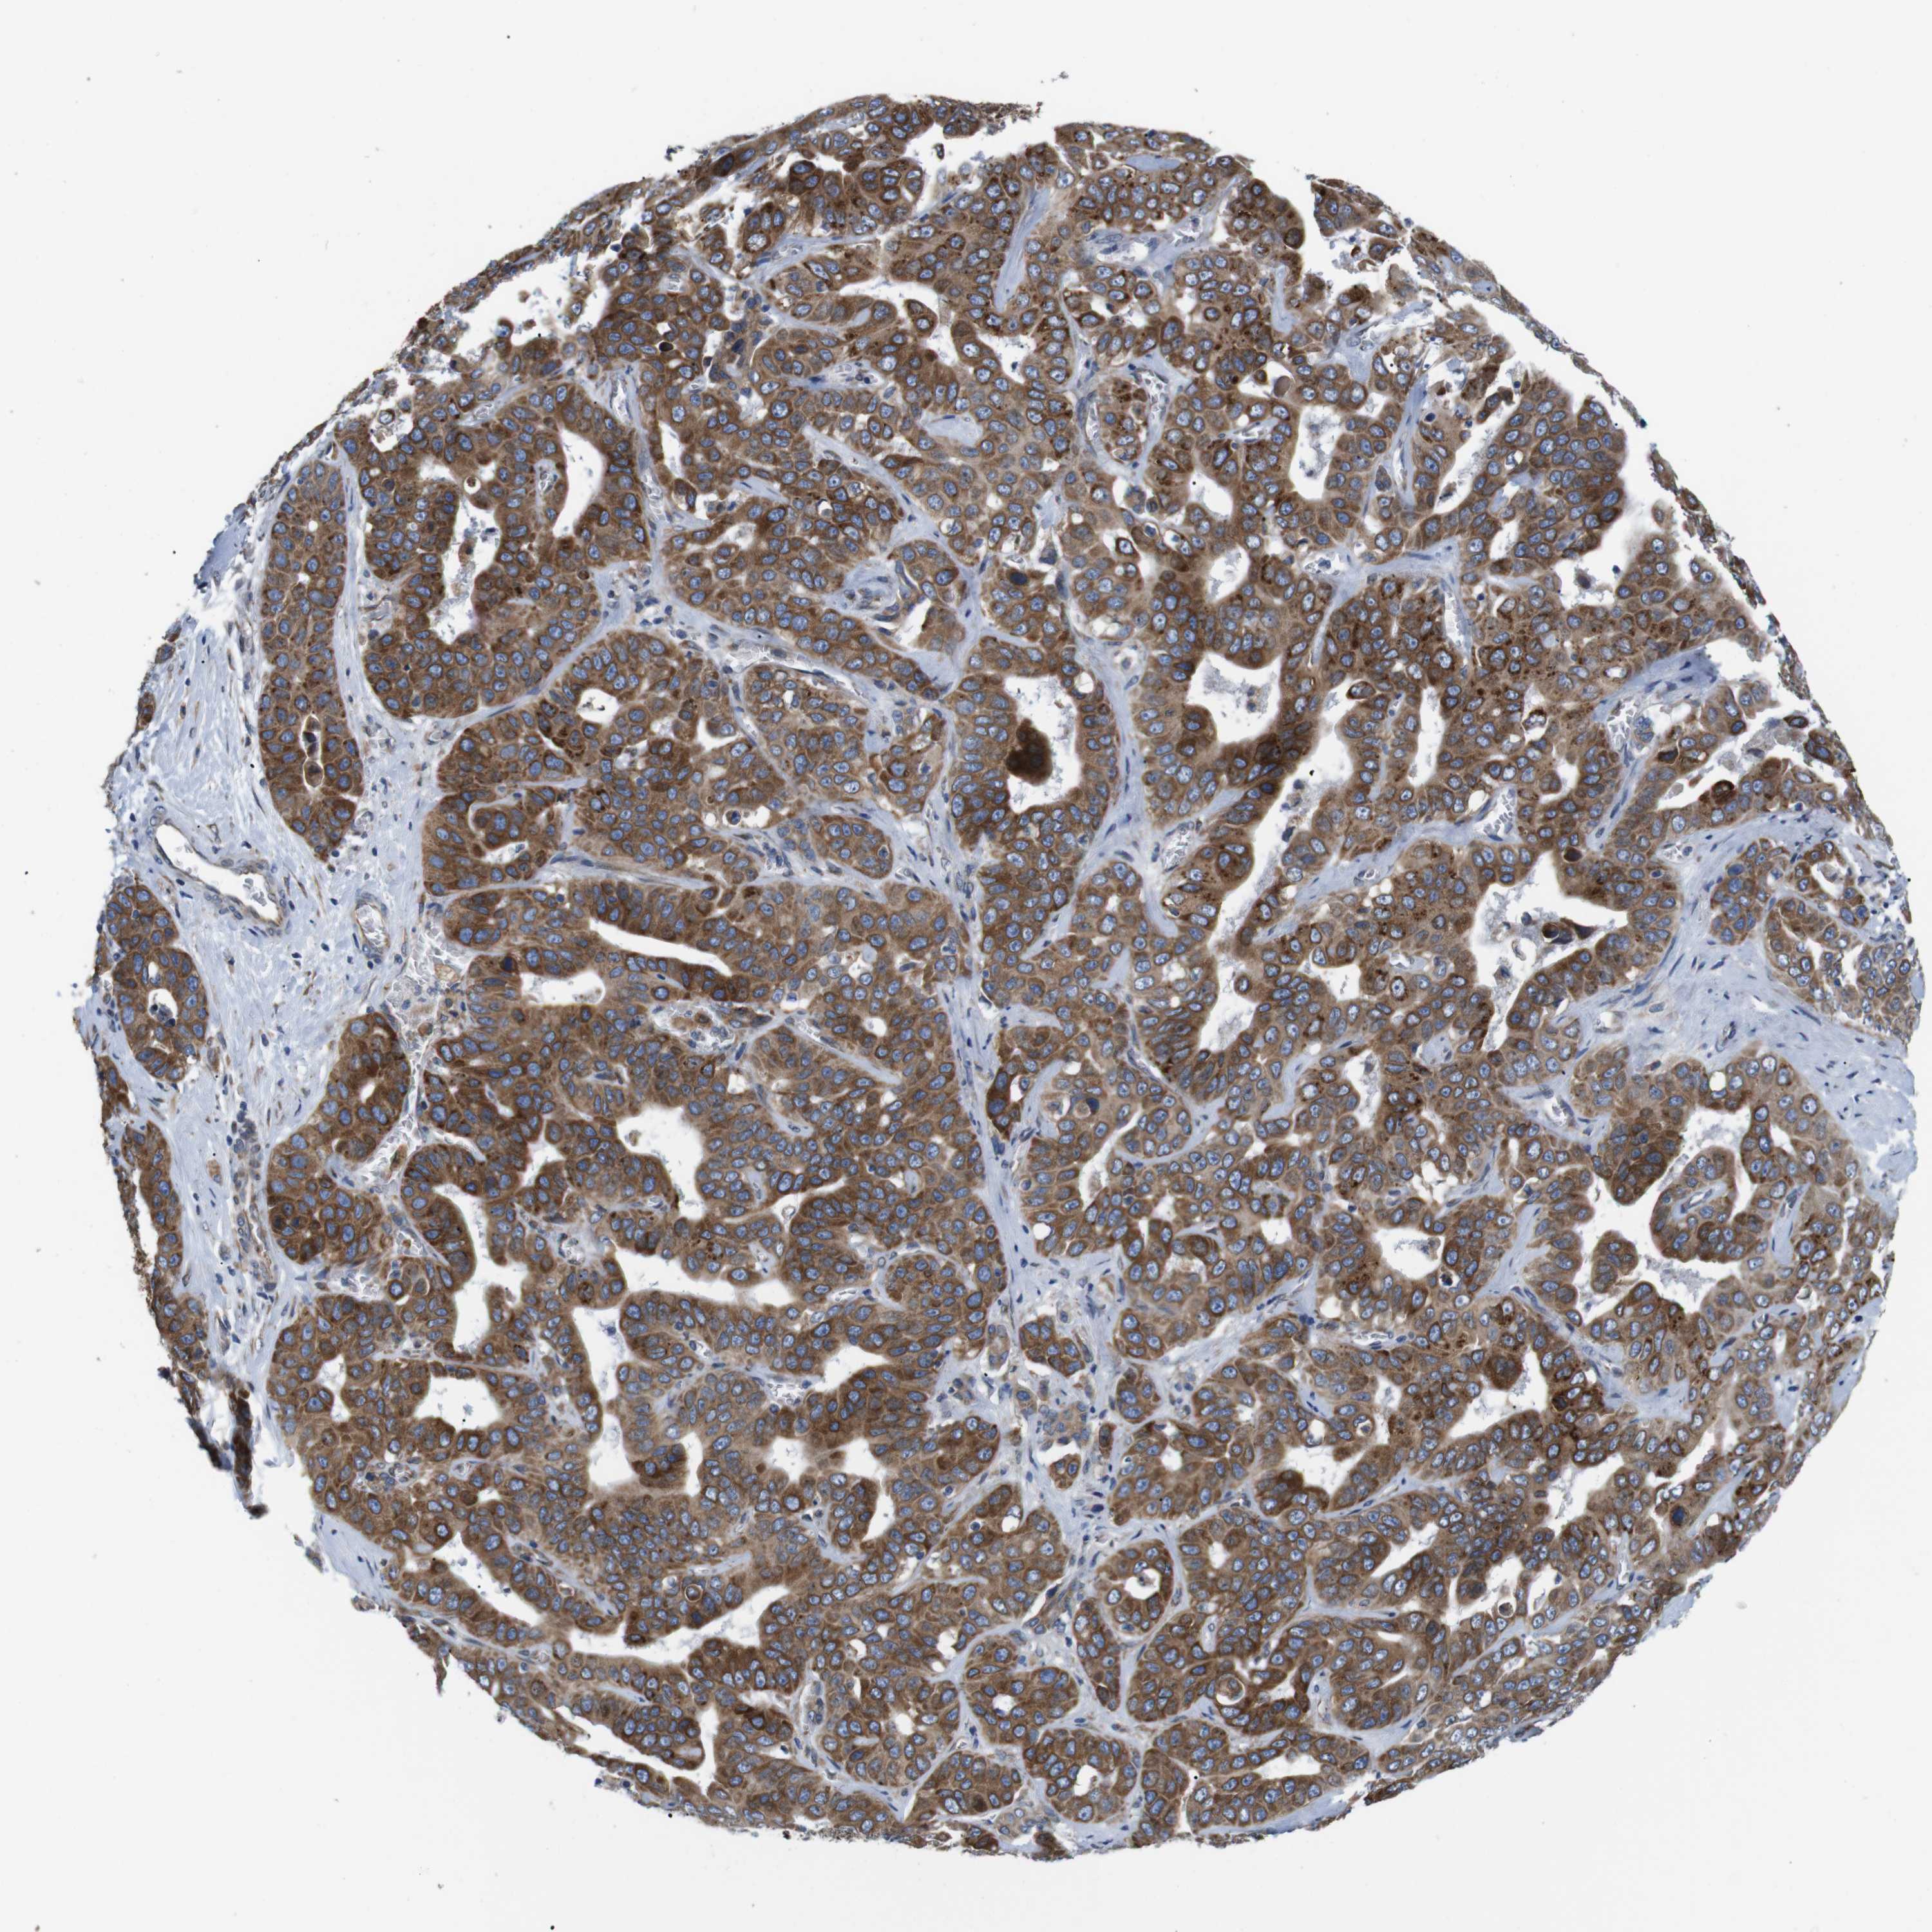

LIVER CANCER - Protein expressioni

A mouse-over function shows sample information and annotation data. Click on an image to view it in a full screen mode. Samples can be filtered based on level of antibody staining by selecting one or several of the following categories: high, medium, low and not detected. The assay and annotation is described here.

Note that samples used for immunohistochemistry by the Human Protein Atlas do not correspond to samples in the TCGA dataset.

Antibody stainingi

Antibody staining in the annotated cell types in the current human tissue is reported as not detected, low, medium, or high, based on conventional immunohistochemistry profiling in selected tissues. This score is based on the combination of the staining intensity and fraction of stained cells.

Each image is clickable and will lead to virtual microscopy that enables deeper exploration of all samples and also displays staining intensity scores, fraction scores and subcellular localization as well as patient and tissue information for each sample.

Antibody HPA014837

Staining

High

Medium

Low

Not detected

Intensity

Strong

Moderate

Weak

Negative

Quantity

>75%

75%-25%

<25%

None

Location

Nuclear

Cytoplasmic/membranous

Cytoplasmic/membranous,nuclear

Cholangiocarcinoma

Carcinoma, Hepatocellular, NOS